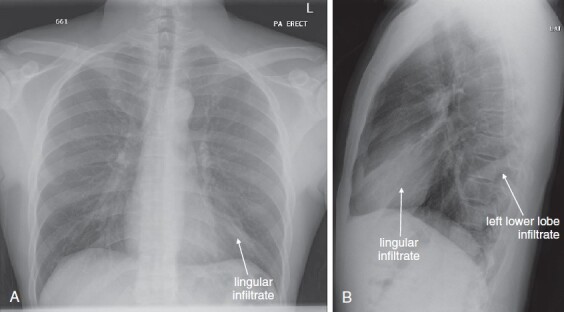

Lateral Upright Chest X-ray View: Retrosternal Space, Retrocardiac Space, and the Spine Sign

The lateral chest x-ray provides important diagnostic information. Unfortunately, this view is usually not obtained when a portable x-ray examination is performed—another good reason to send the patient to the radiology suite for imaging if the clinical condition permits this. The lateral view (Figure 5-16 ) reveals the retrosternal space, which overlies the heart and mediastinum on a frontal projection. This space is usually quite lucent (black) because of the presence of a low-density epicardial fat pad and sometimes lung segments—but when occupied by a soft-tissue mass, this space may appear radiodense (white) (Figure 5-17 ). The lateral chest x-ray also reveals the retrocardiac space. This space normally should be quite lucent (black) (see Figure 5-16). Lower lobe pneumonias may be evident on the lateral view as an abnormally dense retrocardiac region (Figure 5-18 ). On the lateral view, the diaphragms usually form smooth curves descending from anterior to posterior. The space above the diaphragms is usually lucent (black), as it contains low-density lung tissue. Pleural effusions may be evident on lateral view as dense (white) layering opacities replacing the normal curve of the diaphragm in this space (see Figure 5-9). Sometimes pleural effusions form a meniscus against the posterior wall of the thorax, actually reversing the normal curve of the diaphragm. In addition, air beneath the diaphragm (pneumoperitoneum) may be visible on the lateral view (see Figure 5-14).

Figure 5-18.

The spine sign.

The abnormal lateral chest x-ray shows loss of the normal progressive lucency of the thoracic spine as it approaches the diaphragm, called the spine sign. In addition, the retrocardiac space may be less lucent than normal, and the posterior diaphragmatic recess may appear shallow or less lucent than usual, indicating pleural effusion or infiltrate. A, A schematic representation. B, A patient with a retrocardiac infiltrate, illustrating a pathologic spine sign.

The thoracic spine also is visible on a lateral chest x-ray. The normal appearance of the spine is a gradually more lucent (blacker) appearance moving from cephalad to caudad (see Figure 5-16). This is not a result of decreasing spinal density but rather is a normal artifact of the examination technique. When this progressively more lucent appearance is lost, it implies the presence of an abnormal density in the retrocardiac space. This is called the spine sign and is a pathologic abnormality that can be a clue to disease. Remember that the increasing density has a differential diagnosis, including infectious infiltrate, pulmonary edema, pleural effusion, mass, and atelectasis. Other radiographic findings and the patient’s clinical presentation must be used to sort through this differential diagnosis, and additional imaging may be necessary. Nonetheless, this finding can confirm a pneumonia not seen on the frontal projection x-ray. The lateral x-ray is often neglected but is a key additional view that should be obtained whenever possible and carefully reviewed.